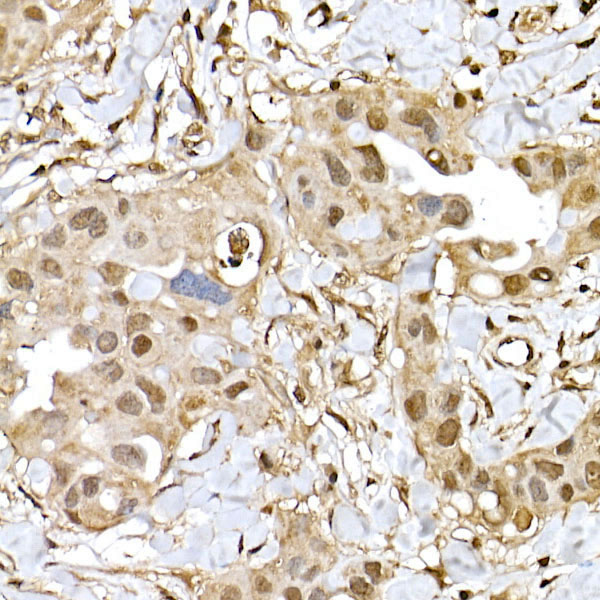

Mammalian target of rapamycin (mTOR) is an atypical serine/threonine kinase that can integrate a variety of extracellular signal stimuli. It is involved in multiple signaling pathways in the body, affecting transcription and protein synthesis. Studies of mTOR found that it has an important connection with processes such as apoptosis, autophagy, and cell growth. For example: 1) mTOR signaling pathway can affect gene transcription and protein synthesis, which plays an important role in cell growth and proliferation. 2) mTOR stability can affect the expression of cytokines in T cells, which is involved in immune suppression. 3) mTOR signaling pathway can affect cell proliferation and protein synthesis, making it a new target for anti-tumor therapy. 4) In addition, mTOR signaling pathway also plays an important regulatory role in diseases such as motor metabolism. mTOR is present in two different complexes, the first being mTOR complex 1 (mTORC1), which consists of mTOR, Raptor, GβL and DEPTOR and is inhibited by rapamycin. The second complex, mTOR complex 2 (mTORC2), consists of mTOR, Rictor, GβL, Sin1, PRR5/Protor-1 and DEPTOR. The function of these two complexes is also different: mTORC1 is responsible for amino acids, oxygen, energy levels, and growth factors, mainly promoting protein synthesis, lipogenesis, energy metabolism, inhibition of autophagy, and lysosome formation. And mTORC2 plays an important role in areas such as muscle Actin cytoskeleton, cell survival, and metabolism.